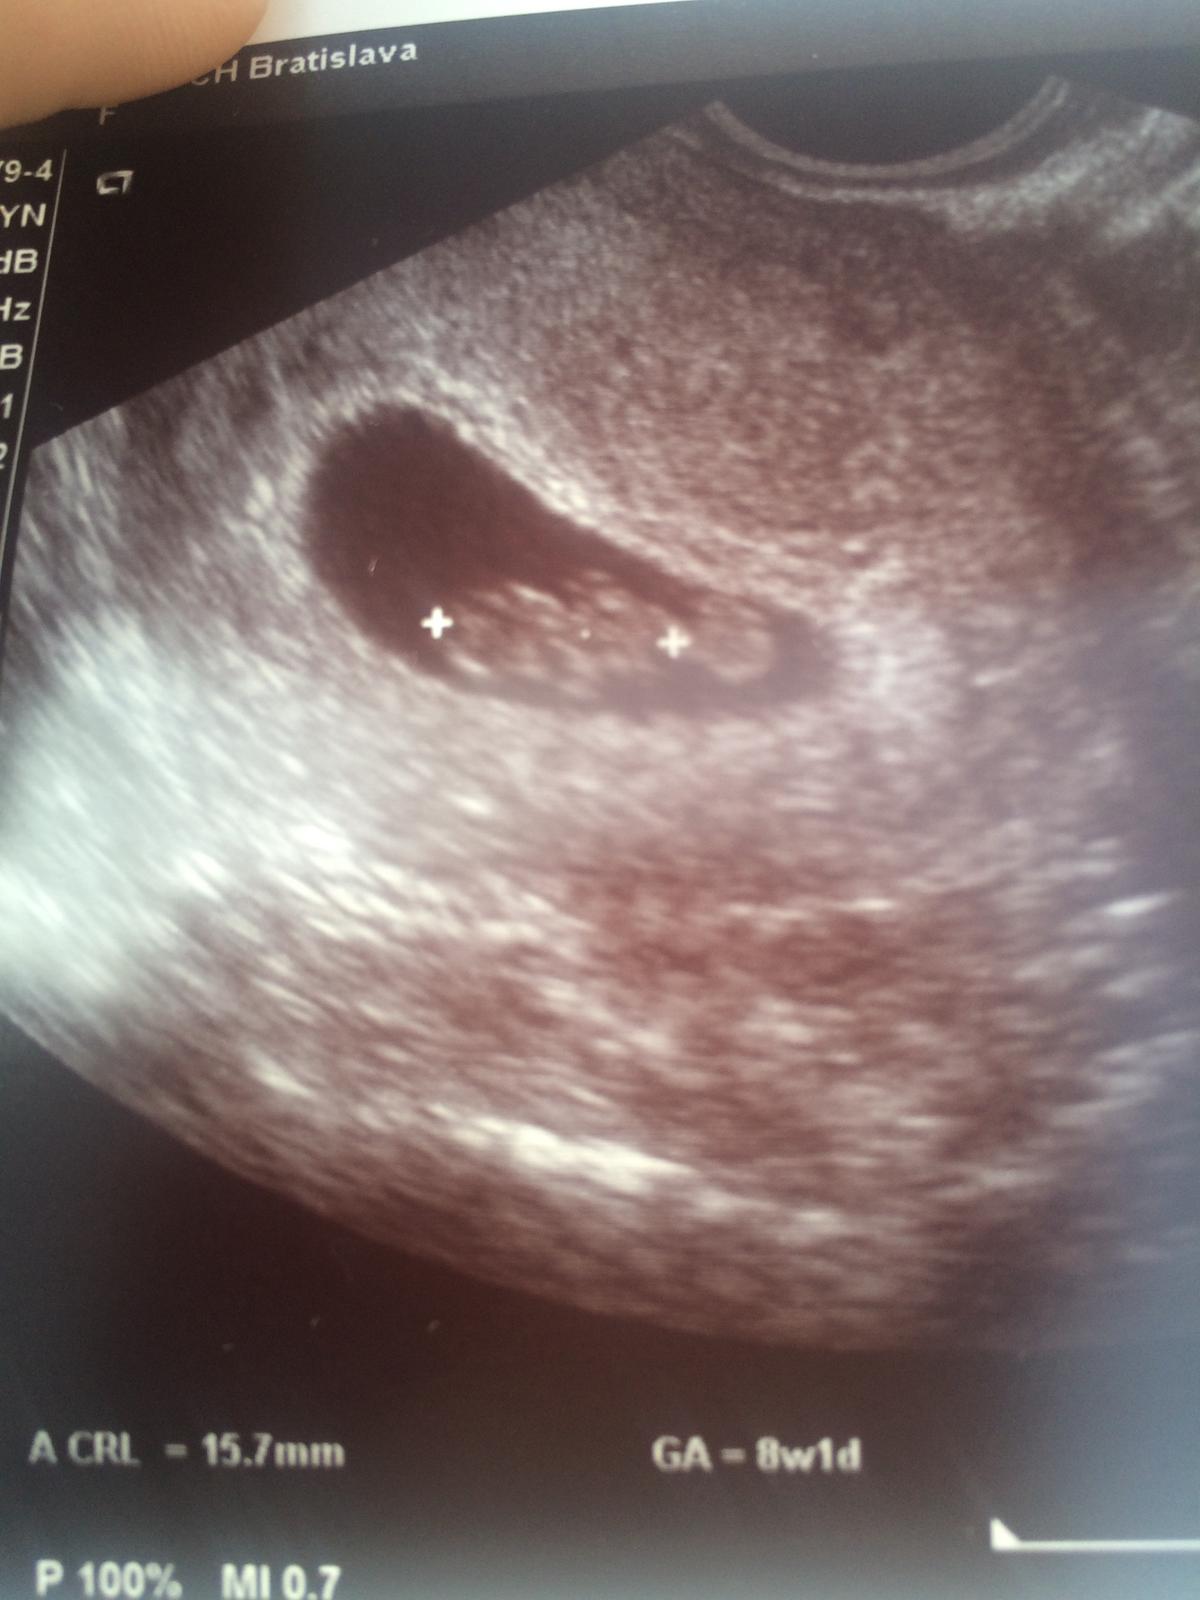

@sara22 no drobec trosku poskocil 🙂, pred dvoma tyzdnami som bola len 5+3 a teraz zrazu ze 8+1, ale lekar hovoril ze merania vacku nie su velmi presne a presnejsie je meranie miminka (takto isto som to mala aj pri prvom 🙂 ). No dalsiu kontrolu mam 15.Dec a 17.Dec idem na NT ultrazvuk